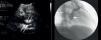

Presentamos el caso de un paciente varón de 11 años de edad, asintomático, remitido a nuestro servicio para estudio por soplo cardiaco. A la exploración física presentaba un soplo continuo 2-3/6 con acentuación diastólica. El electrocardiograma y la radiografía de tórax eran normales. La ecocardiografía (fig. 1) demostró una coronaria izquierda dilatada desde su origen (flechas finas blancas) y con un trayecto tortuoso hacia el seno coronario, dilatado también. En el test de esfuerzo no se apreciaron cambios en el S-T, hipotensión ni eventos arrítmicos. Se programó cateterismo cardiaco en el que se realiza estudio angiohemodinámico habitual que mostró cortocircuito I-D con Qp/Qs=1,6 y valoración inicial de la fístula y su morfología (fig. 1). Tras apreciarse estrechamiento (flechas gruesas azules) en la zona distal de la misma a 7mm de su entrada en seno coronario, se decide el cierre percutáneo con tapón vascular (AVP II de 10mm), que tras test de oclusión con balón y descartar oclusiones colaterales, se liberó en la zona más estrecha de la fístula (fig. 2), con buen resultado, sin cortocircuitos residuales. Se dio de alta al día siguiente con doble antiagregación (acido acetilsalicílico [AAS]+dipiridamol) que se mantuvo durante 6 meses sin incidencias posteriores. Los controles en consultas externas han resultado satisfactorios, sin cambios electrocardiográficos, siendo el test de esfuerzo de control al año del procedimiento normal.